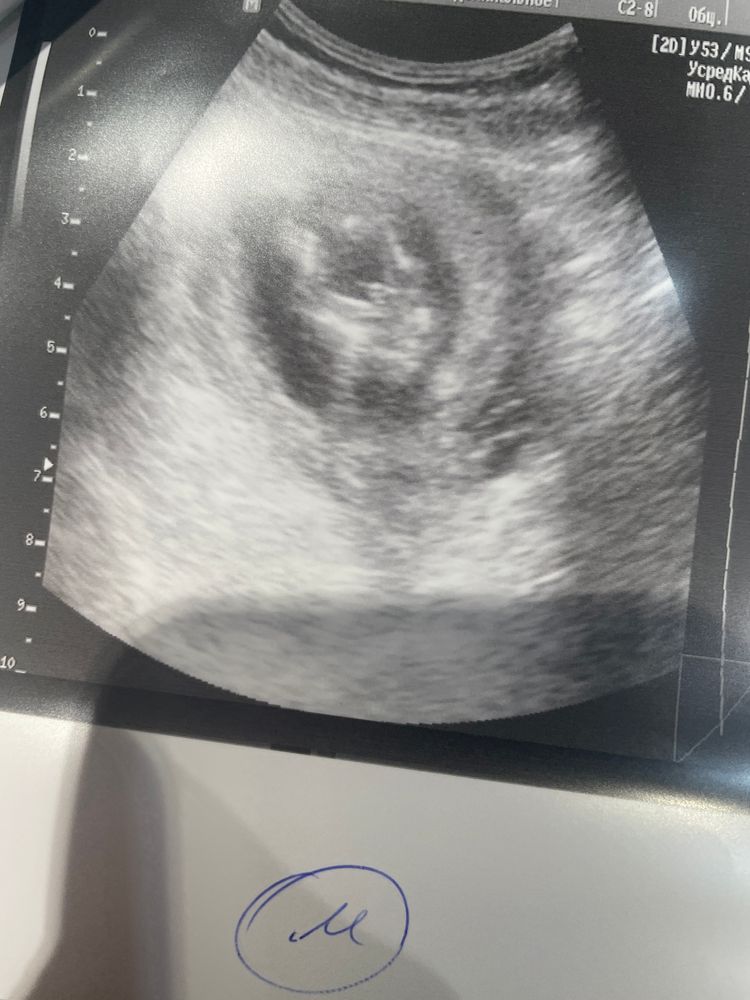

Пол ребенка

Еще половой бугорок, снизу на этом сроке он одинаковый у всех